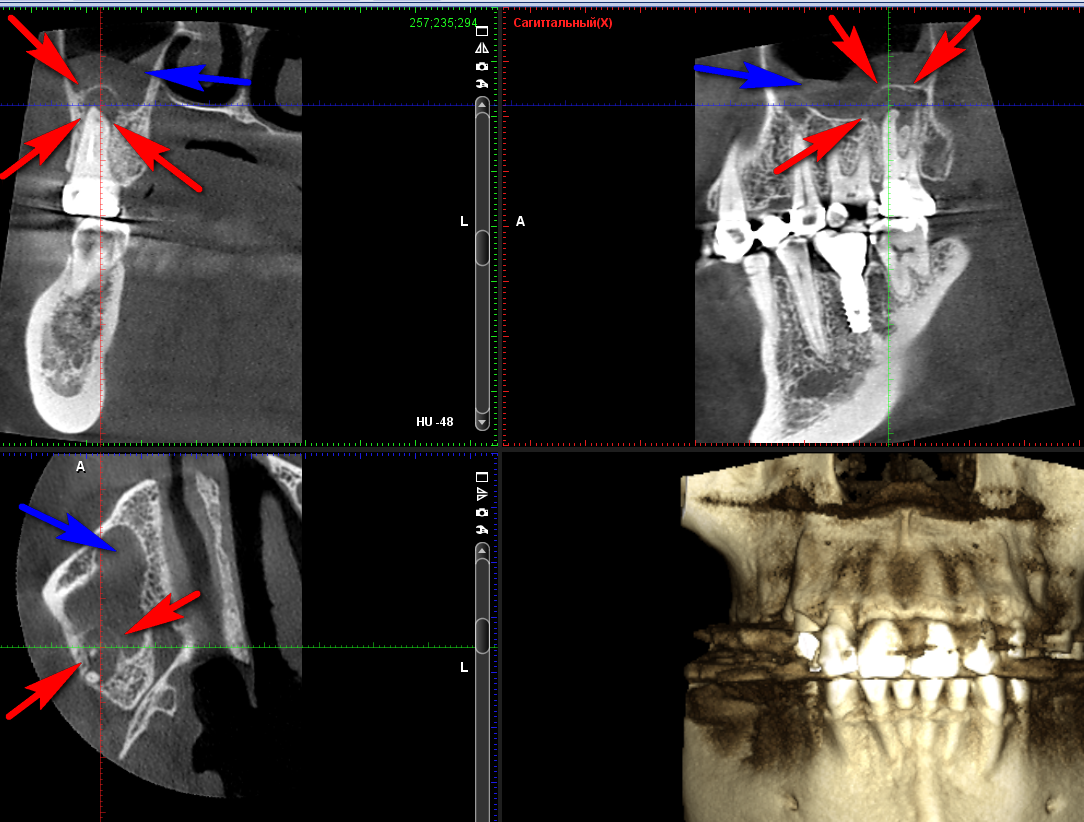

• Очаги хронической инфекции от зубов, чьи корни расположены либо в гайморовой пазухе, либо близко к ней - примерно 30%

• инфицированный пломбировочный материал/инструмент/корень зуба/имплантат, который попал в просвет верхнечелюстной пазухи (гайморовой пазухи) - в этом случае без помощи ЛОР-врача проблему решить скорее всего не получится;